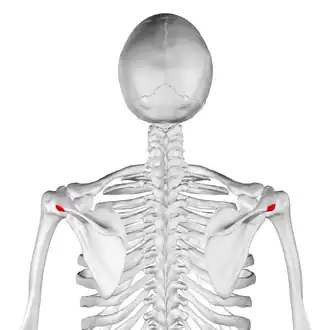

Posterior view. Acromional angle shown in red. | |

Position of acromial angle (shown in red). Animation.

Position of acromial angle (shown in red). Animation. -

Acromial angle is a prominent bony point at the junction of the lateral border of acromion and the spine of scapula.[1][2]